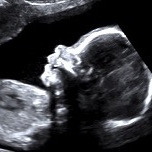

Diplômée en Echographie foetale et Gynécologique

Agrément National pour la réalisation des échographies du Premier Trimestre de grossesse

Membre du Collège d'Echographie Foetale Français (CFEF)